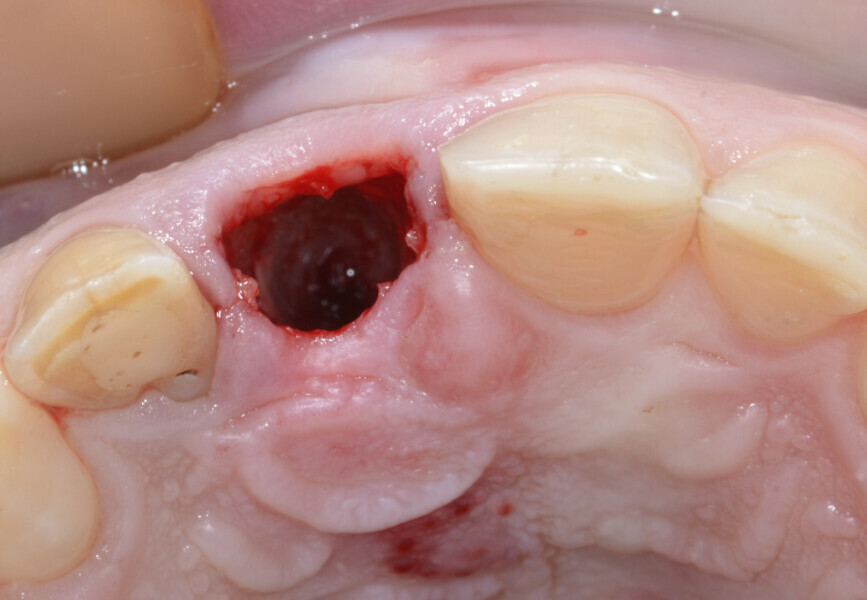

Fig. 11: Clean socket after atraumatic extraction of tooth #11.